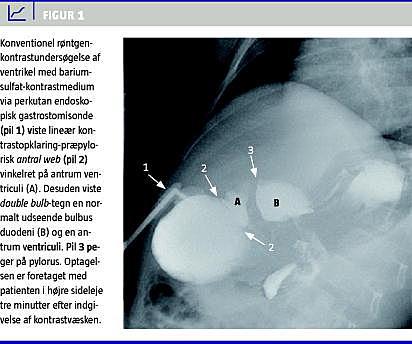

Diagnose af et antral web kan være vanskelig. Diagnosen kunne ikke stilles ved computertomografi og ultralydsskanning i vores tilfælde. Endoskopi kan i nogle tilfælde anvendes til at bekræfte tilstedeværelsen af et antral web . Felson et al [4] gennemgik 39 tilfælde af antral web , hvoraf kun to fik stillet den korrekte diagnose endoskopisk. I vores tilfælde blev barnet gastroskoperet to gange, uden at man kunne stille diagnosen. Konventionel kontrastundersøgelse har relativ stor diagnostisk specificitet [5]. Der kan forekomme svær ventrikelretention, double bulb- tegn og en vedvarende, lineær kontrastopklaring på tværs af antrum ventriculi. Retrospektivt kunne vi genfinde double bulb- tegn i vores tilfælde (Figur 1).